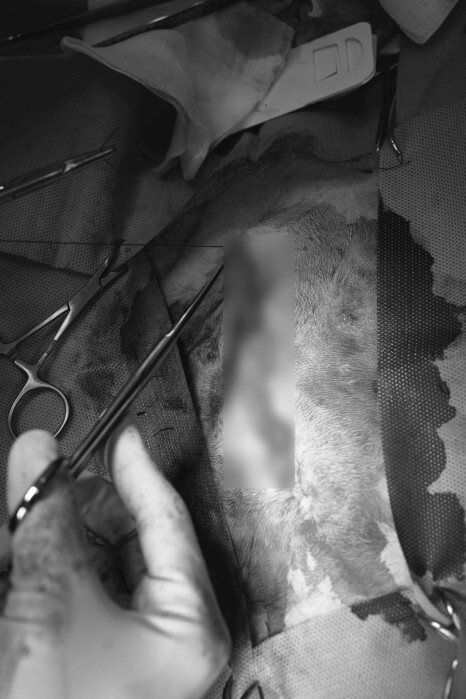

수술을 위해 배 부위의 털을 정리하고 나니 더욱더 확연하게 드러난 볼록 솟은 배입니다.

수술 도구가 등장합니다.

보기만 해도 차갑고 날카로움이 연상이 됩니다.

정확한 위치를 잡고 개복을 합니다.